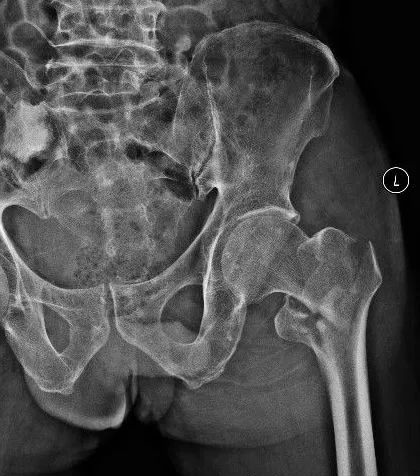

髓内钉内固定装置示意图 老年股骨颈骨折的主要手术治疗方式为人工股骨头置换和全髋关节置换。

因为操作简单、手术时间短、创伤相对全髋关节置换小,对于80岁以上患者,偶尔户外活动的超高龄患者可考虑单纯的人工股骨头置换术。相对于人工股骨头置换术,全髋置换术适用于身体条件较好、较健康、对功能恢复要求较高、活动量大、对生活质量要求较高的患者。

人工股骨头和人工全髋关节置换装置